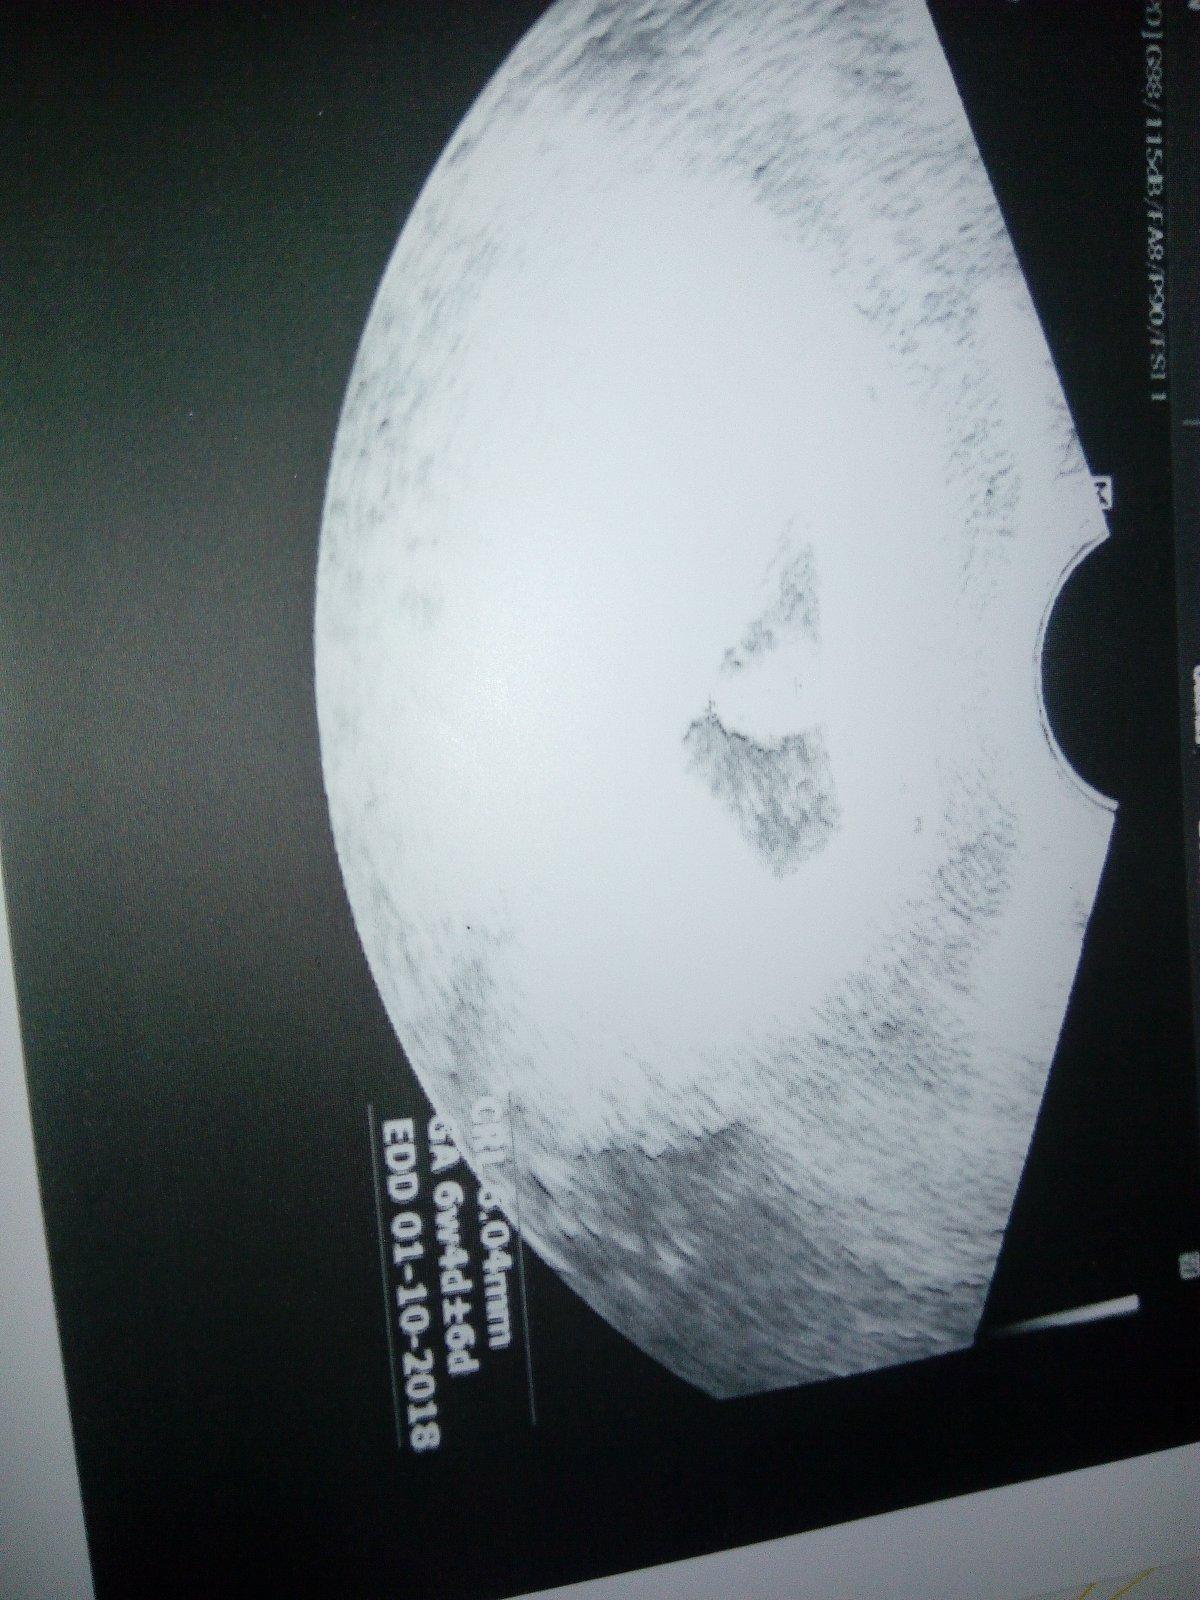

Ahoj tak u doktorky těhotenství potvrzeno, mimco velikosti odpovida a dostala jsem prukazku. Srdicko mi sice poslechnout nedala, vlastne ho ani nezminila, ale slova v prukazce jeden zivy plod mluvi jasne, kontrola za mesic a ještě se musim objednat na screening do gennetu, protoze jsem odmitla jit k Apolinari ze se tam bojim :D